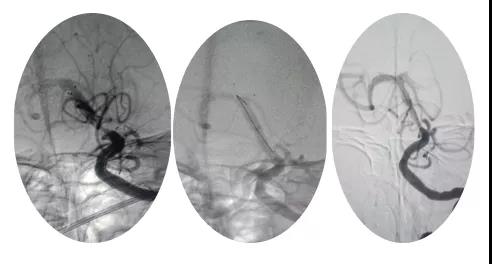

18:30手術開始,造影為基底動脈閉塞,與患者家屬充分溝通,患者家屬同意給予介入取栓治療。共取栓2次,取出少量暗紅色血栓塊。造影示:基底動脈有重度狹窄,結合患者病情演變及造影結果,考慮為動脈粥樣硬化性狹窄。根據患者造影結果,目前單純取栓無法達到預期效果,決定給予基底動脈支架植入術。根據患者基底動脈直徑選擇3.0*13mm apollo球擴支架,支架植入后造影示狹窄消失。

支架植入后患者神志轉清,四肢均可活動,左側肢體活動略差于右側,收入神經內四科病房進一步治療。術后第三天患者神志清,四肢活動基本正常,住院5天轉入當地醫院治療。?